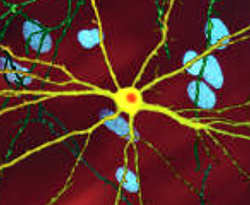

| Medium spiny neurons (yellow) with nuclear inclusions, which occur as part of the disease process, stained orange | |